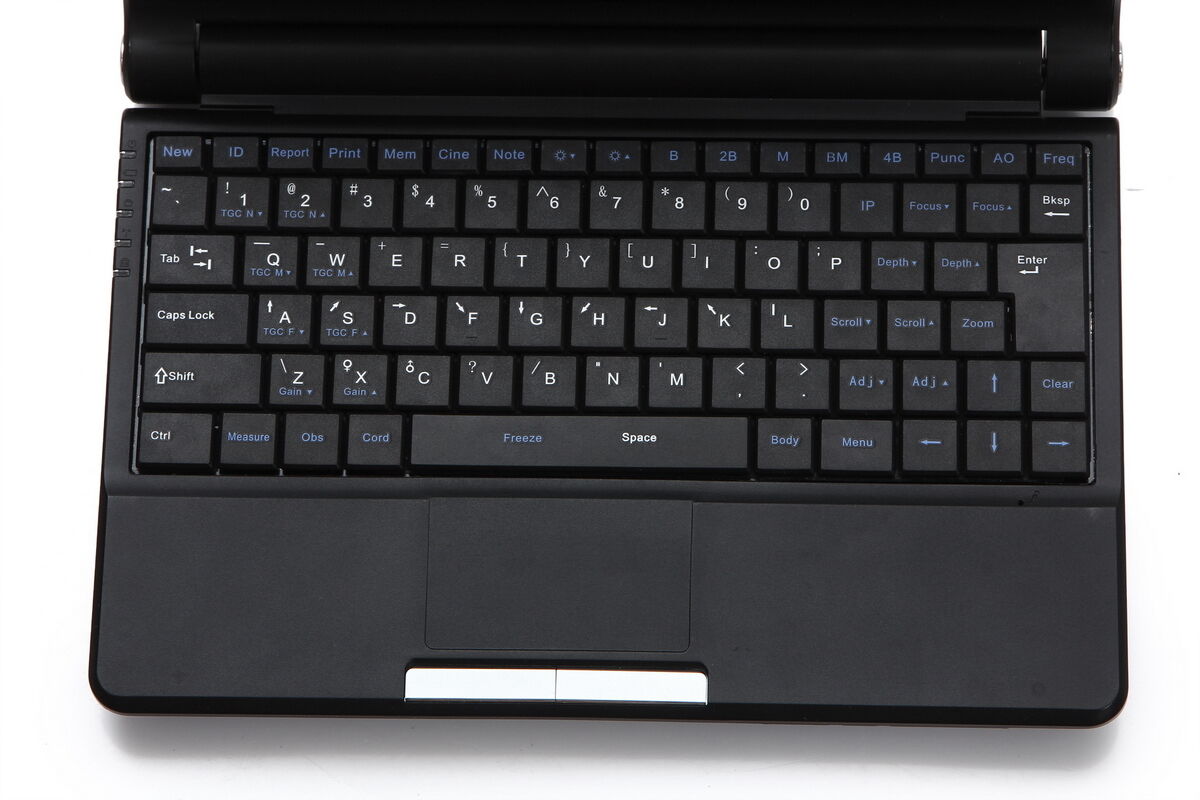

In terms of user interface, the TFT LCD Digital Laptop Linear Array Ultrasound Scanner comes with intuitive software that allows operators to navigate through different settings and functions effortlessly. This reduces the learning curve and means even new users can quickly become proficient in its use. The software is regularly updated, ensuring that you have access to the latest features and improvements.